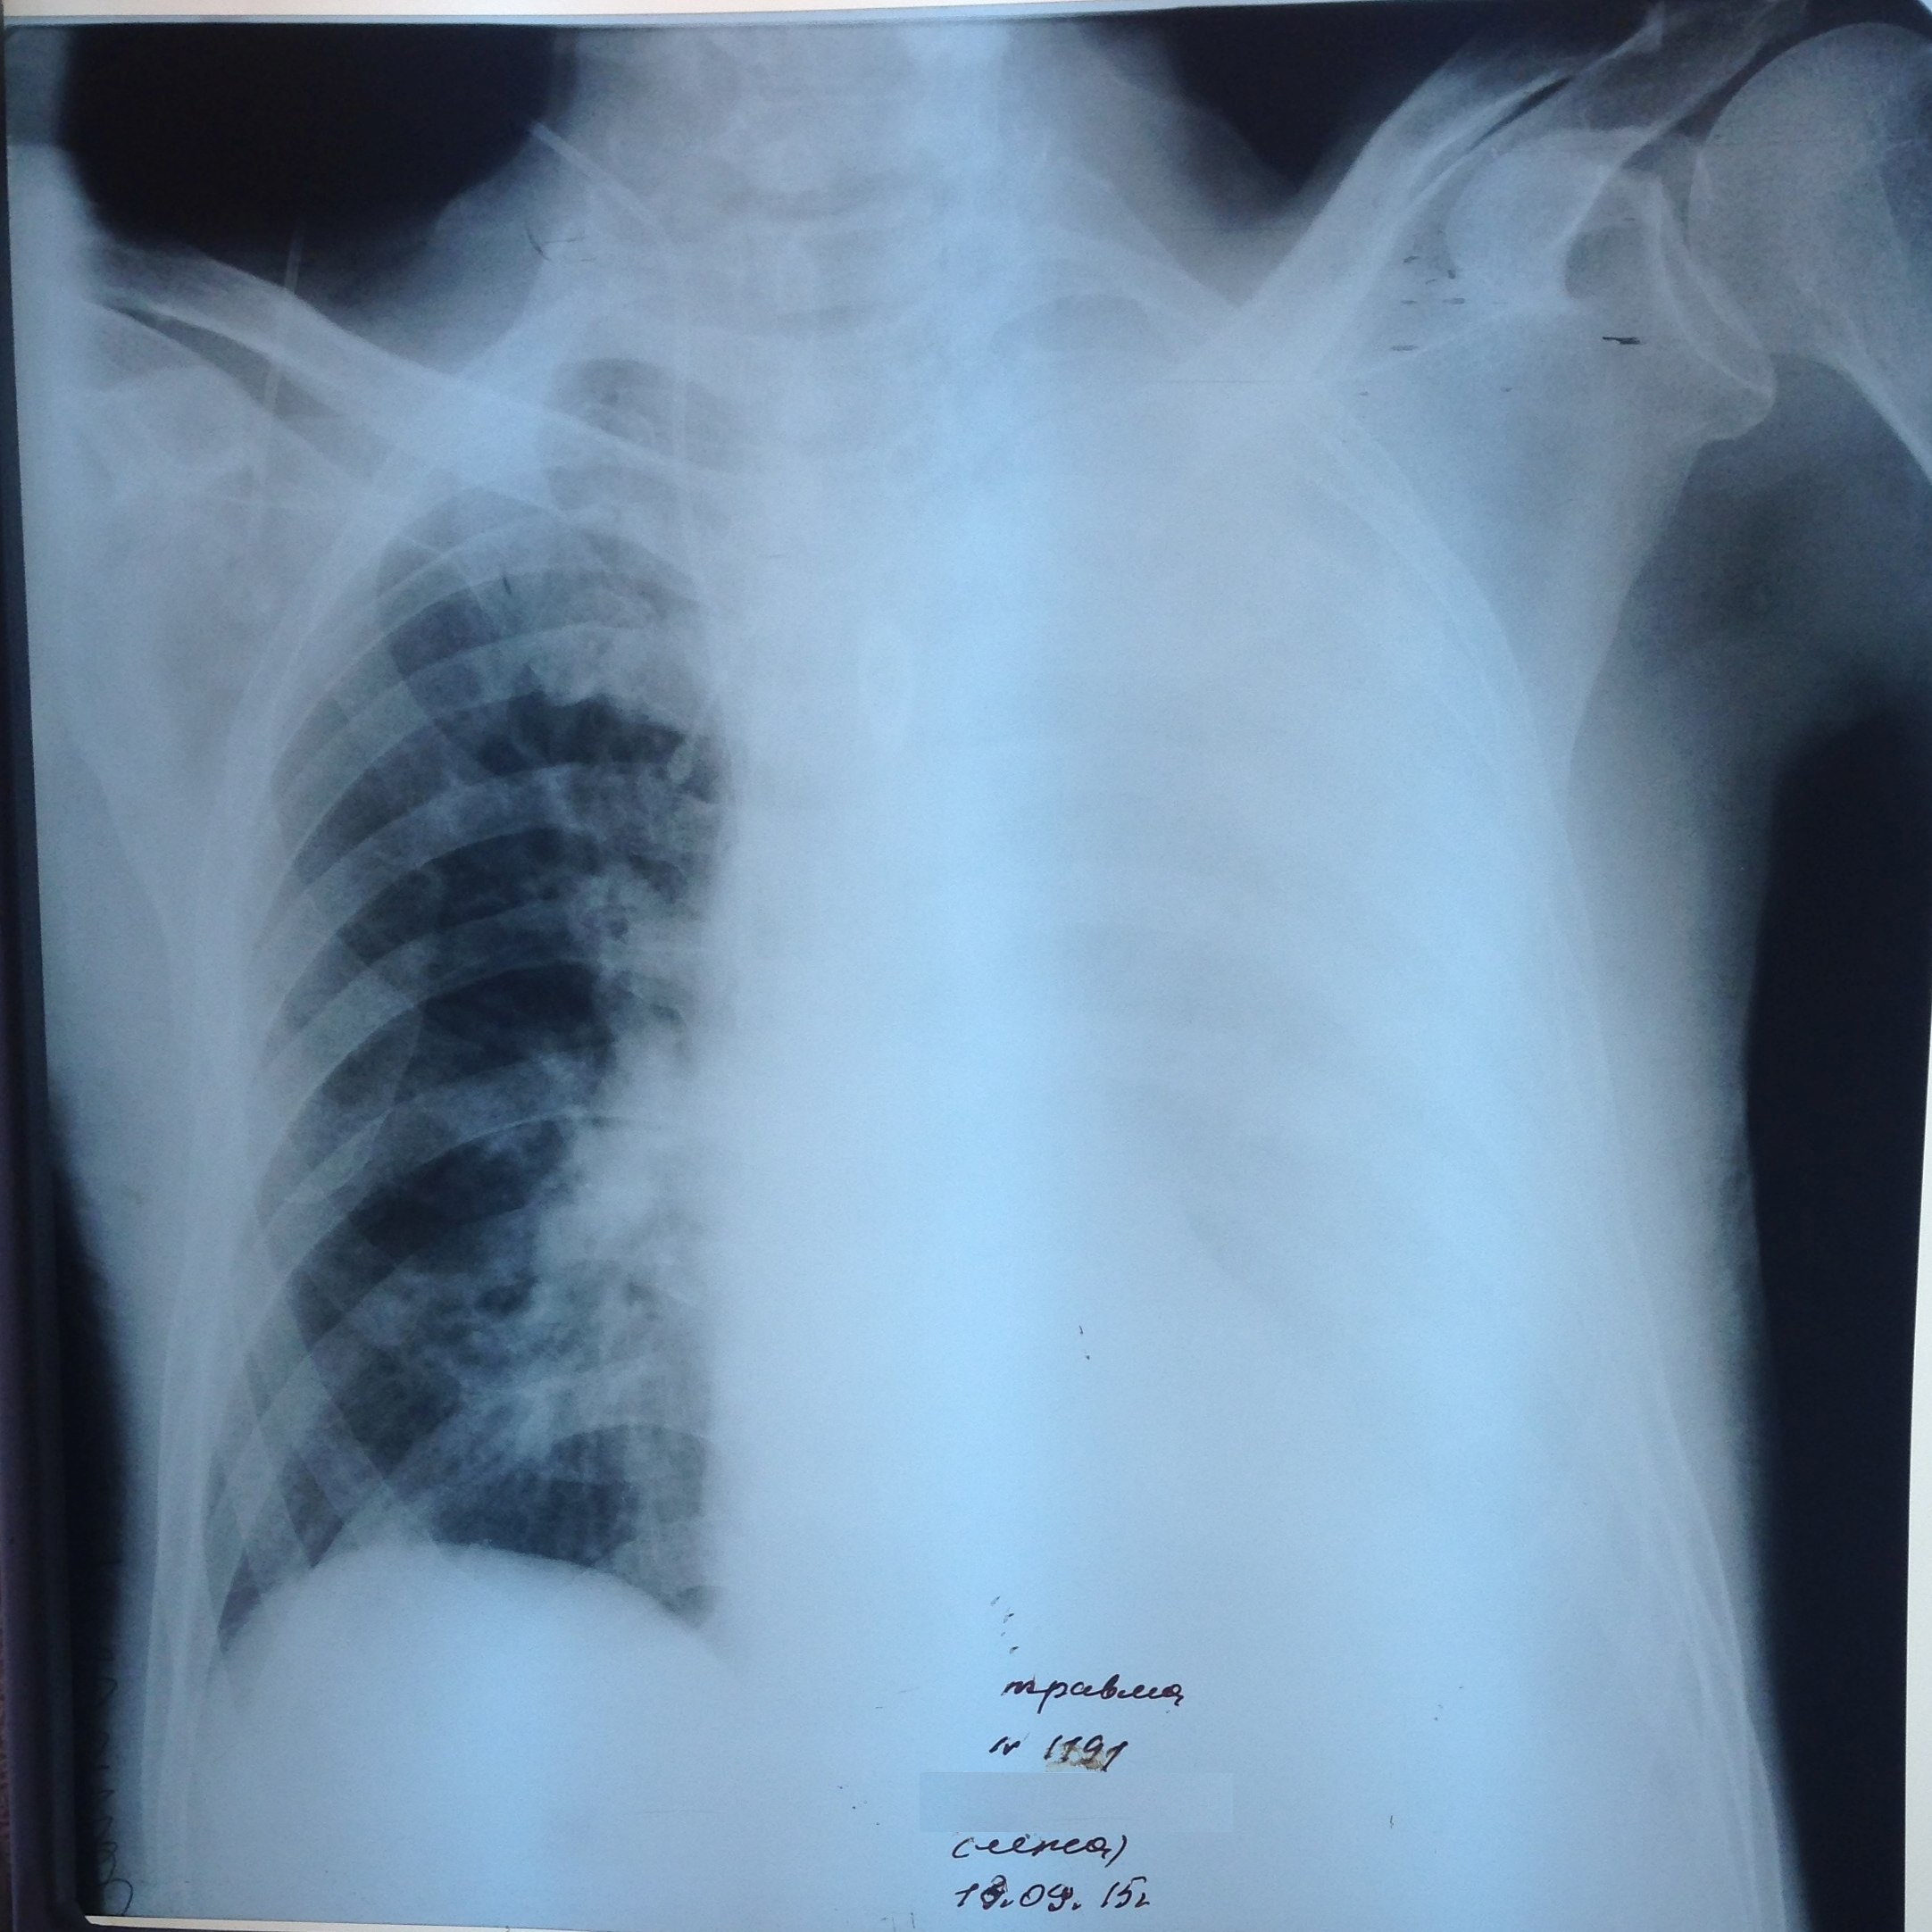

Тотальное затемнение слева - жидкость. Но жидкости не так и много. Всё-таки просматривается легочная ткань и при пункции получено всего 400 мл. Сидя в этом случае надо делать снимок. Или чтобы объем жидкости подсчитали спецы УЗИ.

Не обсуждалось